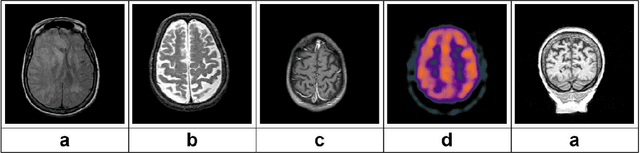

Abstract:Early-stage 3D brain tumor segmentation from magnetic resonance imaging (MRI) scans is crucial for prompt and effective treatment. However, this process faces the challenge of precise delineation due to the tumors' complex heterogeneity. Moreover, energy sustainability targets and resource limitations, especially in developing countries, require efficient and accessible medical imaging solutions. The proposed architecture, a Lightweight 3D ATtention U-Net with Parallel convolutions, LATUP-Net, addresses these issues. It is specifically designed to reduce computational requirements significantly while maintaining high segmentation performance. By incorporating parallel convolutions, it enhances feature representation by capturing multi-scale information. It further integrates an attention mechanism to refine segmentation through selective feature recalibration. LATUP-Net achieves promising segmentation performance: the average Dice scores for the whole tumor, tumor core, and enhancing tumor on the BraTS2020 dataset are 88.41%, 83.82%, and 73.67%, and on the BraTS2021 dataset, they are 90.29%, 89.54%, and 83.92%, respectively. Hausdorff distance metrics further indicate its improved ability to delineate tumor boundaries. With its significantly reduced computational demand using only 3.07 M parameters, about 59 times fewer than other state-of-the-art models, and running on a single V100 GPU, LATUP-Net stands out as a promising solution for real-world clinical applications, particularly in settings with limited resources. Investigations into the model's interpretability, utilizing gradient-weighted class activation mapping and confusion matrices, reveal that while attention mechanisms enhance the segmentation of small regions, their impact is nuanced. Achieving the most accurate tumor delineation requires carefully balancing local and global features.